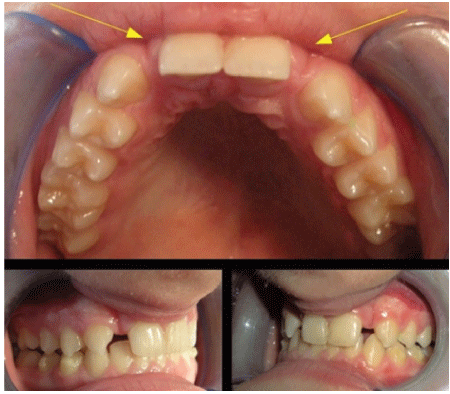

The second report deals with a 28-y.o. female patient, Caucasian, in a good health status, suffering from agenesis of the upper lateral left incisor, in bilateral class one, with a right canine mesialization, which affected the natural lateral space closing it.

The patient was treated with Invisalign® invisible aligners from September 2007 until July 2008, using overall 25 aligners. The pictures above show the results obtained by the orthodontic treatment with 4.6 mm of space gained for the lateral incisor. On July 15th, 2008, she underwent an implant procedure, after that an immediate acrylic provisional crown was placed during 2 months. After that, a definitive crown made of the same materials as stated before was placed and has been regularly followed-up between 2007 and 2016 (Figures 9-14).

Figure 9: Lack of the upper lateral tooth in a young female patient.

Figure 10: Gaining space allowed to set the bicortical screws with a small opening flap.